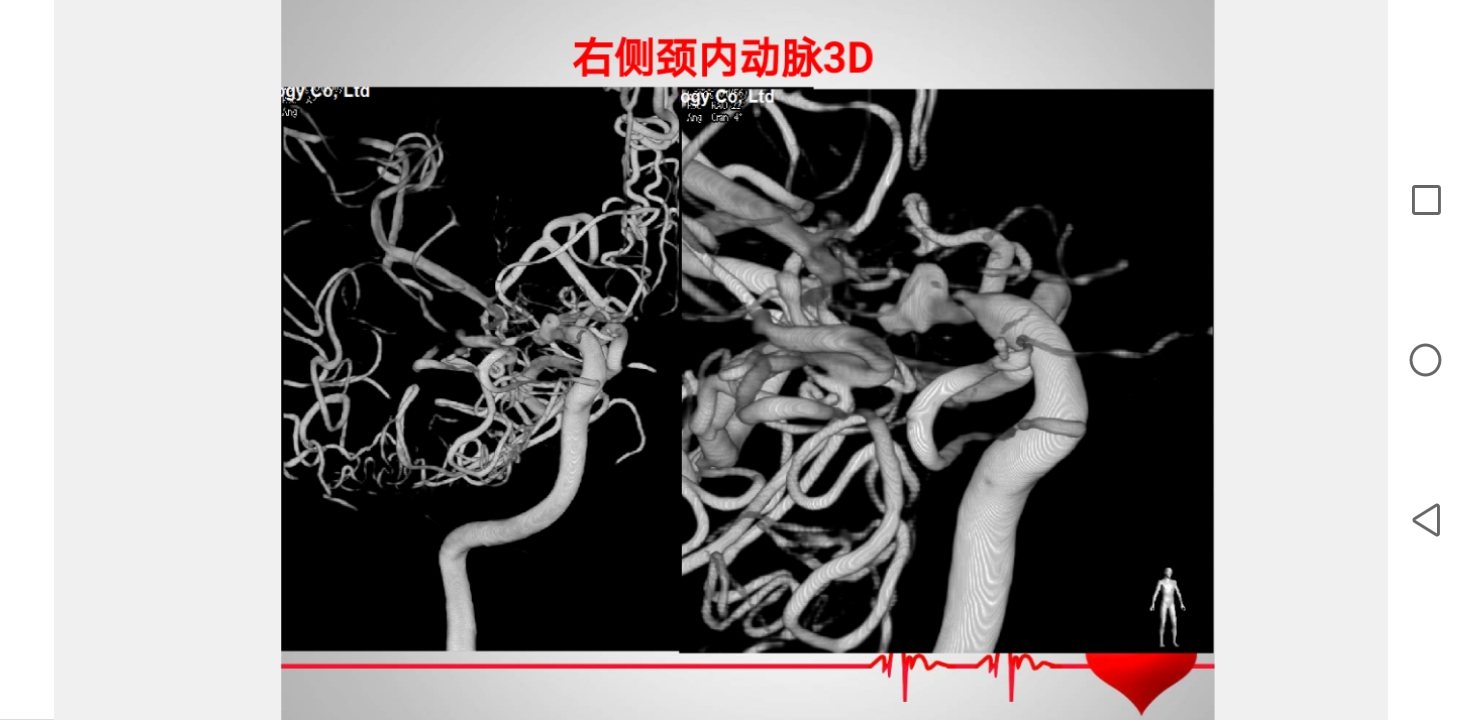

脑血管造影3D成像

脑血管造影3D成像